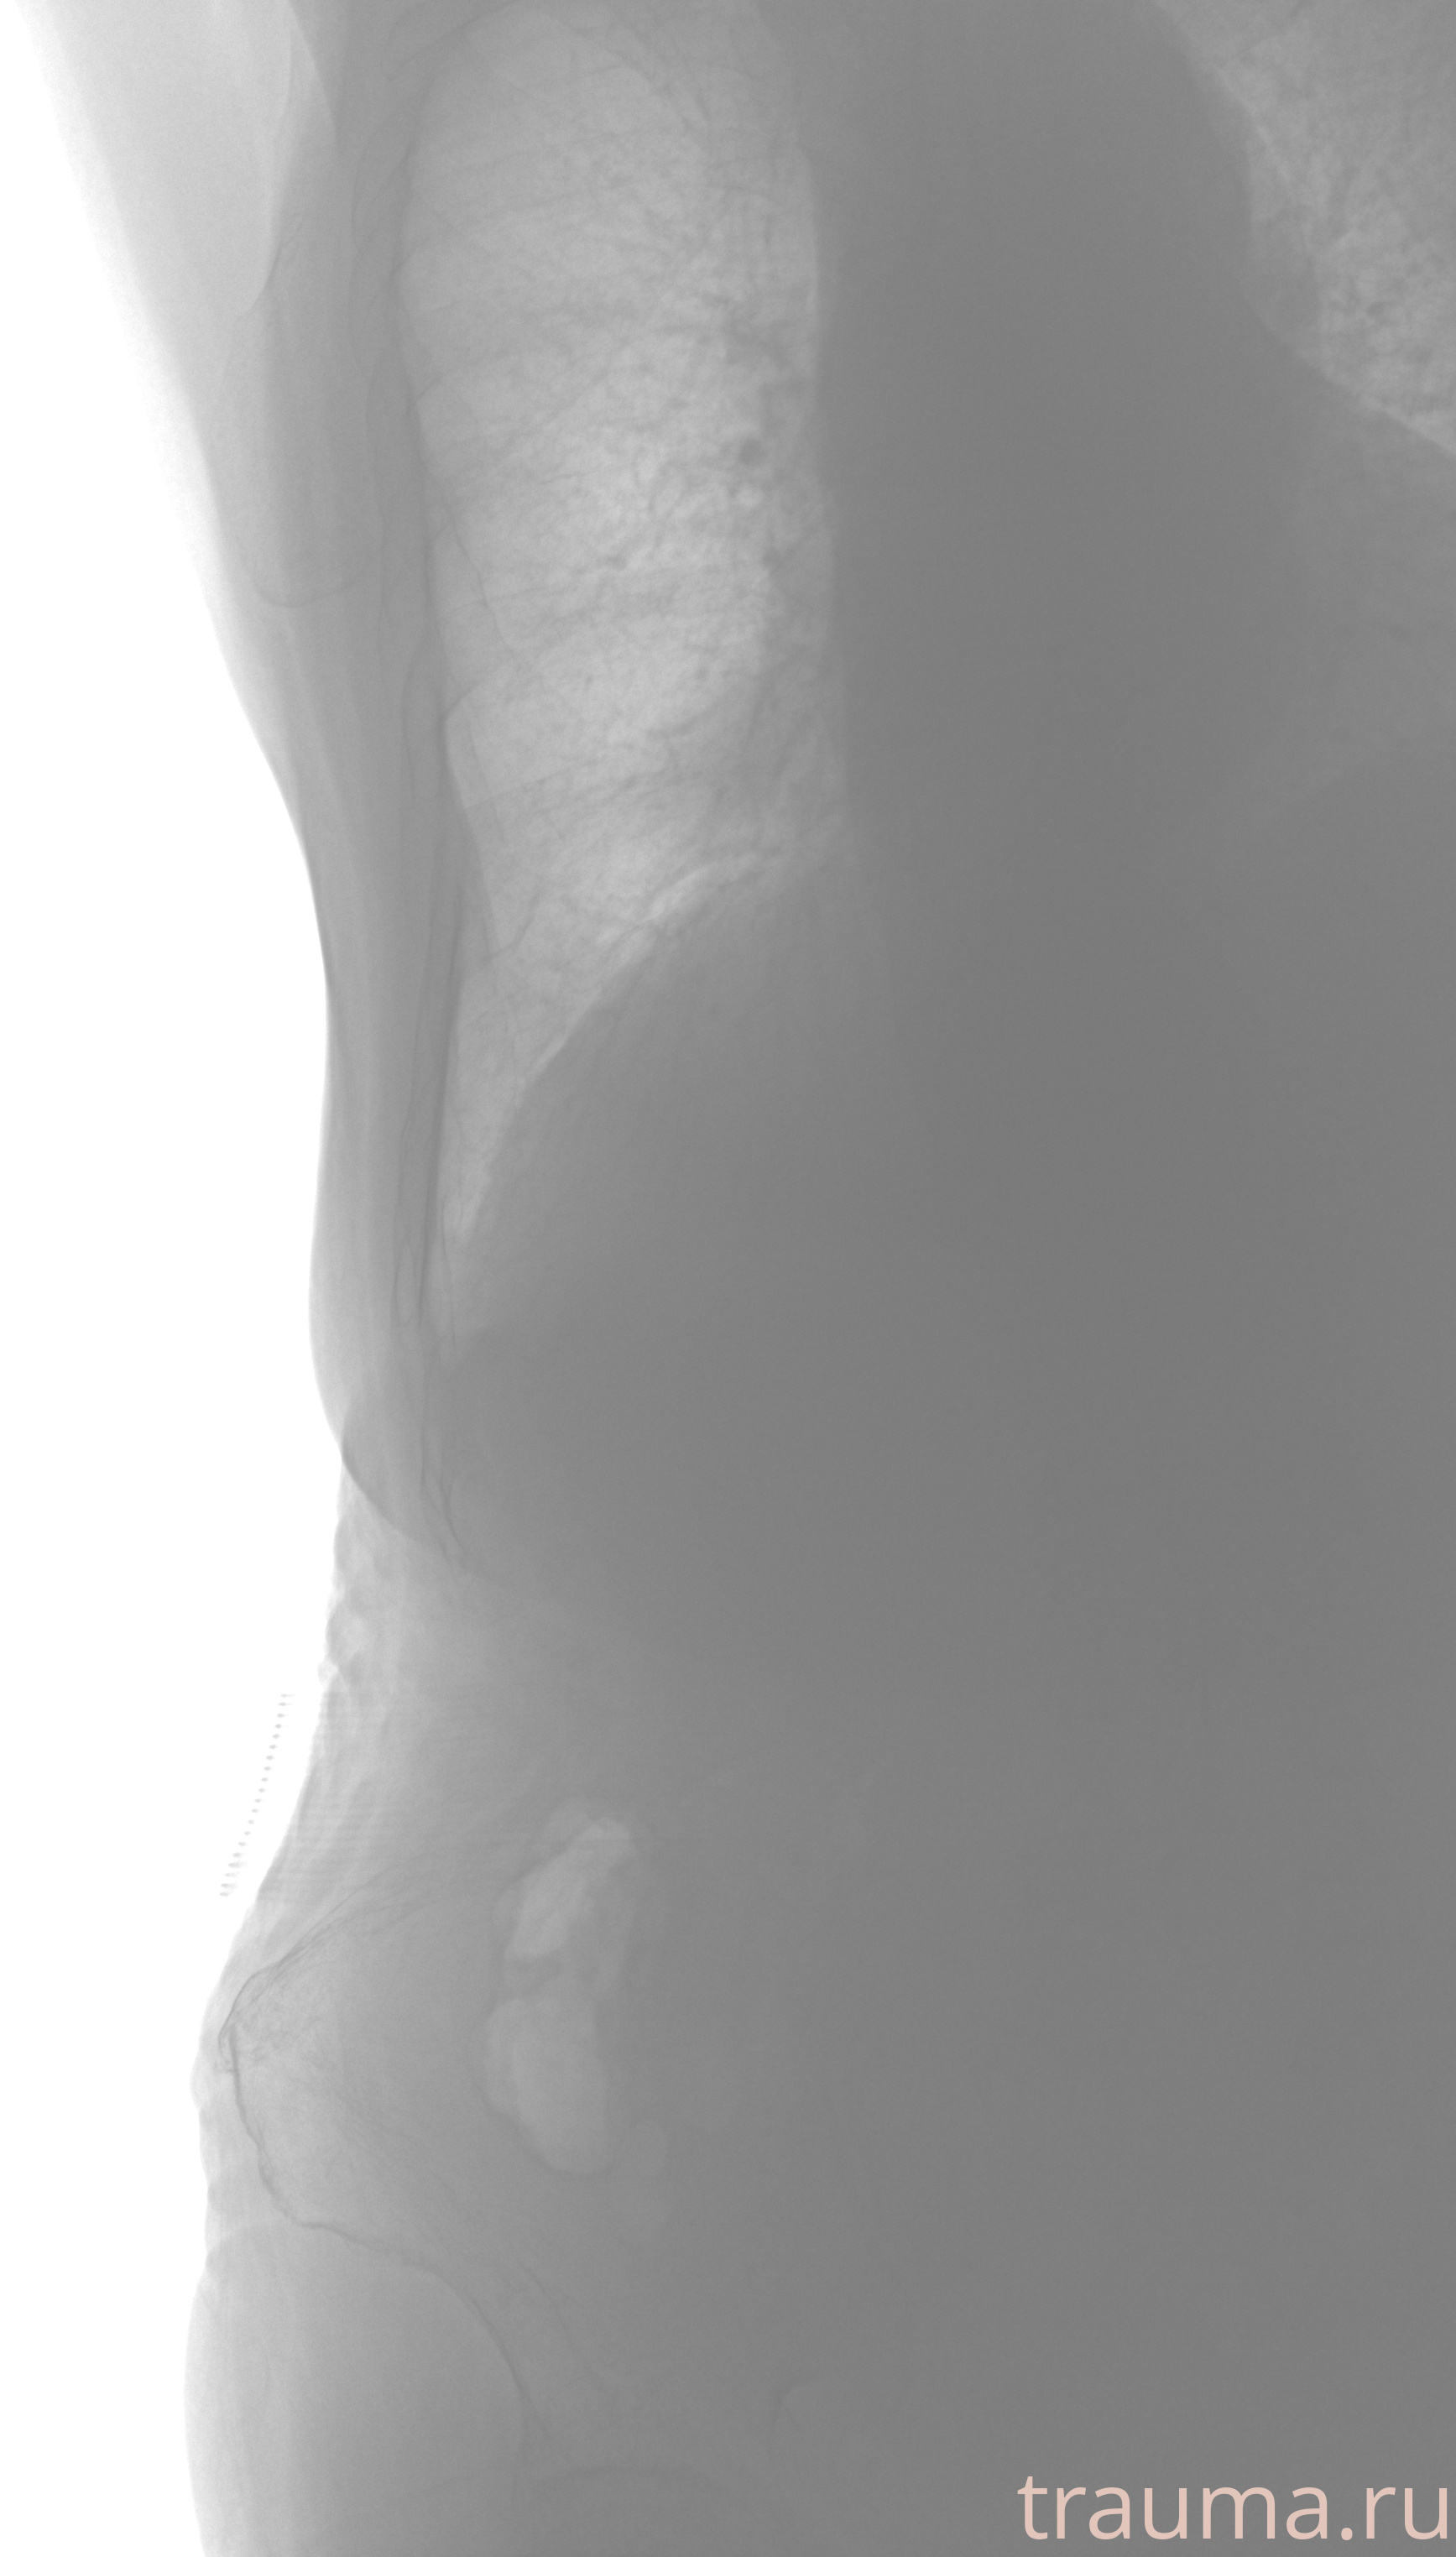

Рентгенограммы

Рентген на дому: по вашему адресу приезжает врач-рентгенолог, травматолог-ортопед с мобильным рентгеновским аппаратом, проводит диагностику травмы или заболевания, делает необходимые рентгенограммы, дает рекомендации по дальнейшему лечению. Получить качественные снимки в домашних условиях возможно благодаря уникальной методике, разработанной МосРентген Центром для института  Склифосовского

при переломе шейки бедра и пневмонии от компании МосРентген Центр - партнера Института имени Склифосовского